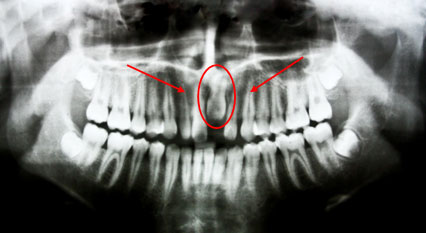

Samples of panoramic x–rays

*This is a panoramic x–ray of an eight–year old patient with odontoma. Odontoma was surgically removed and tooth was orthodontically pulled out.

*This is a panoramic x–ray of a six–year old patient with an extra inverted tooth which was surgically removed to close the gap of the incisor.

*This panoramic x–ray shows an impacted central incisor which is dilacerated or has a bent root that needs to be surgically and orthodontically pulled out.